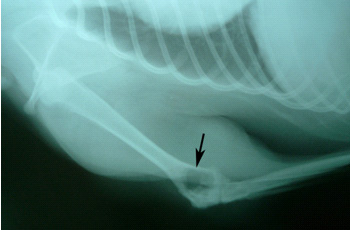

经X线初步检查显示:右前肢肘关节附近有骨质溶解(见图1),失去骨小梁,异常骨组织边缘不整齐,病变组织还未超过生长板。肺片未见明显异常,疑似骨肉瘤

图 1 右前肢X线片。肱骨远端大范围溶解性病变(箭头所指区域)。